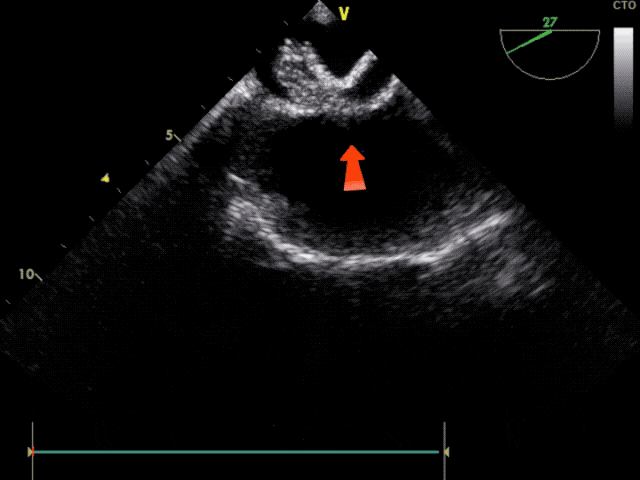

左盘展开

于左心房中部展开封堵器左盘

整体后撤鞘管和钢缆,使左盘贴靠

轻拉成型线,使左盘成型

锁定前观察

锁定前观察,确认封堵器骑跨于房间隔两侧,稳固夹持